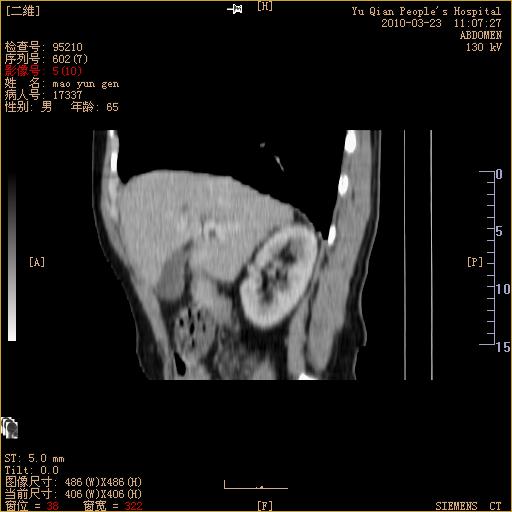

标题: CT25266:消瘦月余,前来肝部检查,请看看肠腔 [打印本页]

标题: CT25266:消瘦月余,前来肝部检查,请看看肠腔

升结肠肠壁增厚,不均强化,考虑升结肠腺癌可能性,建议肠镜检查。

1)考虑升结肠癌。2)右肾小囊肿。